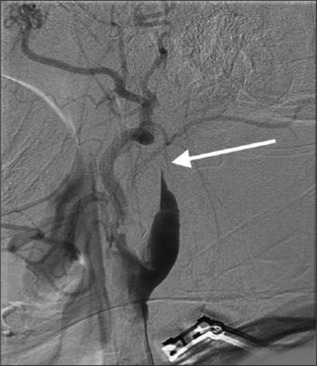

Carotid endarterectomy (CEA) is an established method of stroke prevention in patients with severe carotid artery stenosis, especially in those with symptomatic disease. Complications of CEA include perioperative stroke, cranial nerve palsy, hemorrhage, and vascular dissection. We present an unusual case of a 66-year-old man who presented for elective right CEA for symptomatic 70% right internal carotid artery (ICA) stenosis due to ulcerated plaque. Following surgery, the patient developed fluctuating neurological deficits consistent with involvement of the right middle cerebral artery territory. Imaging revealed possible mild clamp-induced ICA dissection limited to the ICA in the neck. Despite initial successful anticoagulation management in the neurointensive care unit, the patient returned 2 days later with stroke symptoms, necessitating urgent endovascular intervention. Neurovascular interventions involved aspiration thrombectomy and multiple stenting extending distally into intracranial ICA, which successfully restored cerebral arterial perfusion and normal neurological function. This case highlights the first reported instance of extensive intracranial ICA dissection managed with full-length stenting. This article offers an effective endovascular procedure for preventing a devastating stroke from a complication of a procedure that was performed to prevent it.